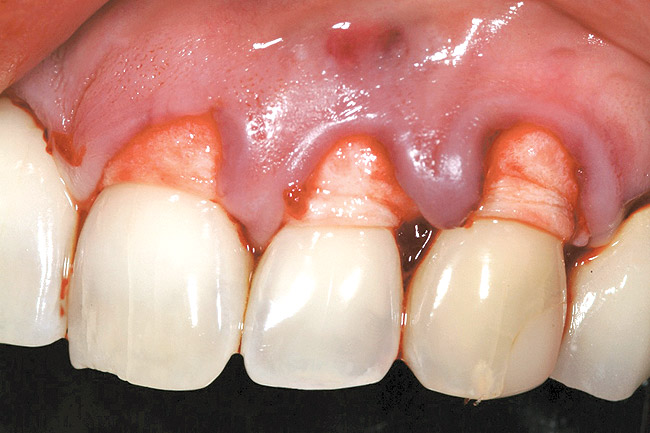

A 54-year-old non-smoking woman presented for correction of deep-wide gingival recession in the maxillary anterior (Figure 1 through Figure 3). The patient’s desires were to correct the gingival recession, balance the heights of contour of the tissues, and possibly undergo esthetic enhancement of the maxillary anterior with veneer restorations.

Figure 1  Case One Pretreatment clinical view, Case 1, maxillary right.

Figure 1

Figure 2  Case One Pretreatment clinical view, Case 1, maxillary anterior.

Figure 2